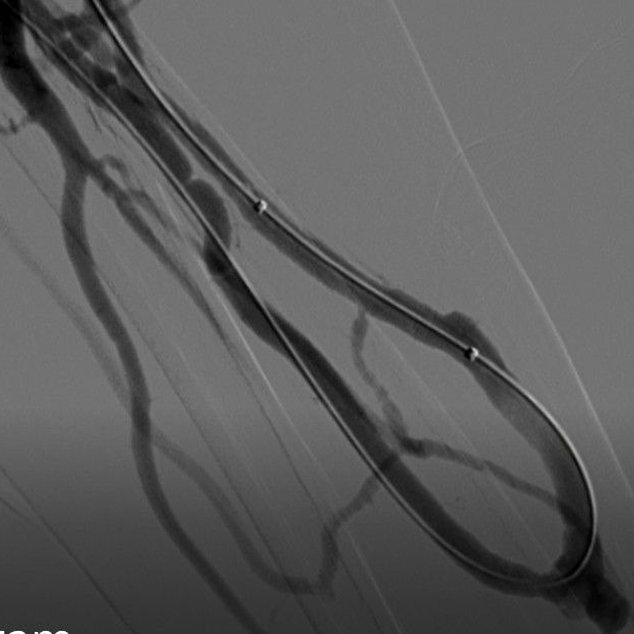

Fistula narrowing or blockage with facial swelling (central vein occlusion) and abnormal flow.

Restoring blood flow in blocked or dysfunctional AV fistulas.

Portal hypertension , bleeding and Cirrhosis, Budd Chiari management.